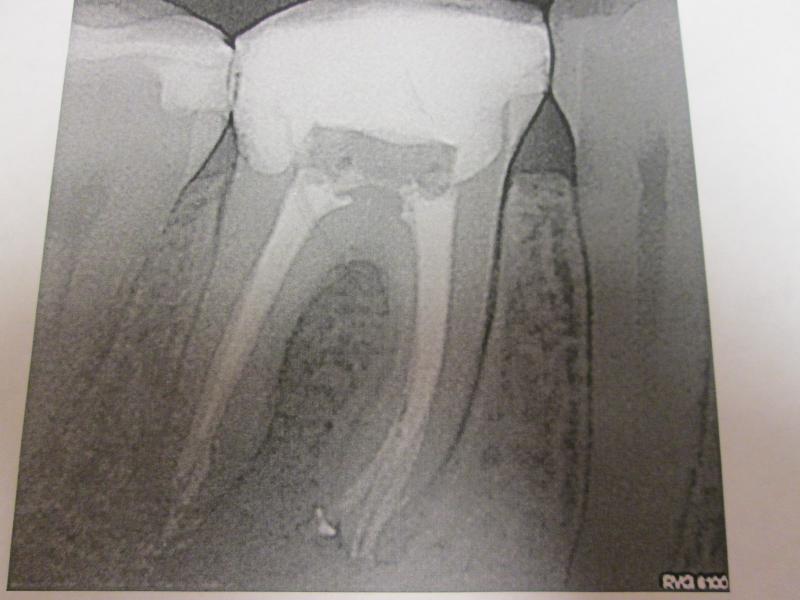

DR JET LOVES ROOT CANALS

"DR. JET'S MISSION IS TO PERFORM  ROOT CANALS FOR A REDUCED FEE USING THE LATEST TECHNOLOGY  AND TECHNIQUES TO SERVICE THE MANY PEOPLE WHO ARE UNINSURED OR UNDER-INSURED GIVING EVERYONE AN OPPORTUNITY TO SAVE THEIR TOOTH!"

ROOT CANALS by DR. JET (Jetepon Chiranand DDS)